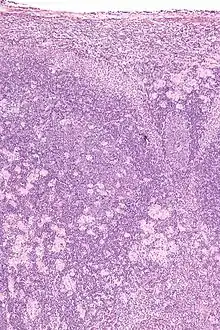

Toxoplasmosis cannot be detected with immunostaining. Lymph nodes affected by Toxoplasma have characteristic changes, including poorly demarcated reactive germinal centers, clusters of monocytoid B cells, and scattered epithelioid histiocytes.